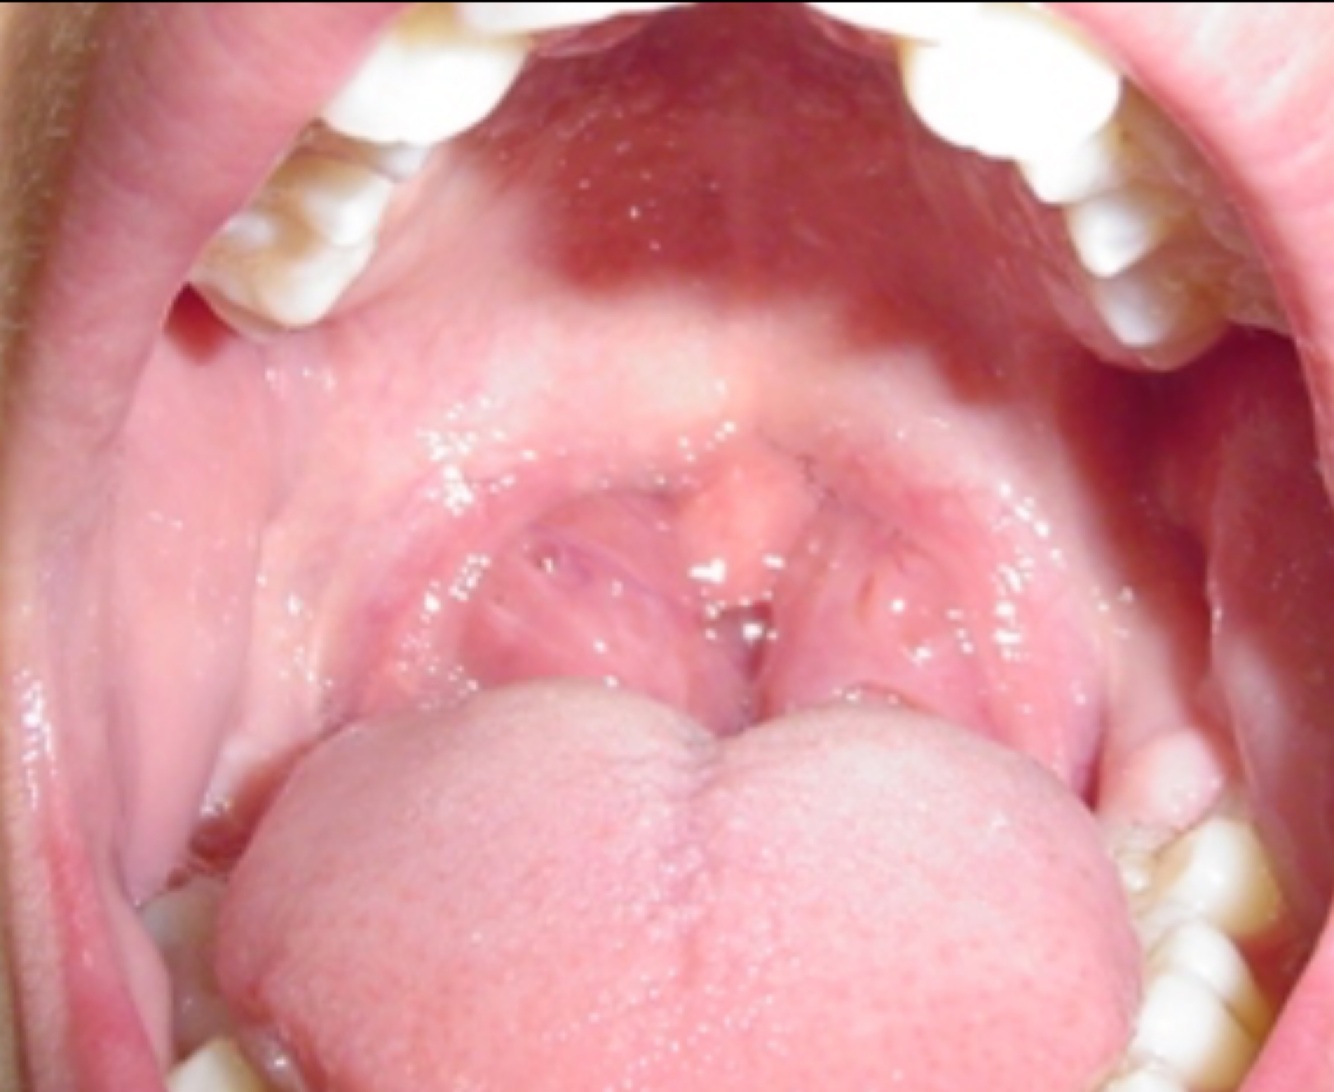

Amigdalitis viral

Dx